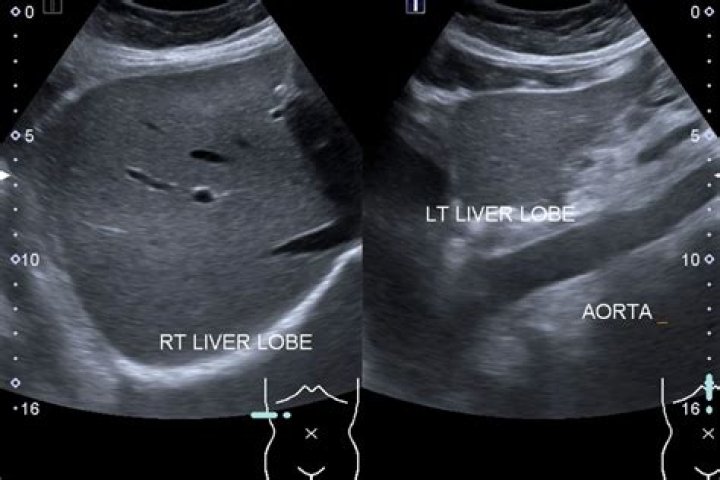

Coarsened hepatic echotexture is a sonographic descriptor where there uniform smooth hepatic echotexture of the liver is lost. This can occur due to numbe...